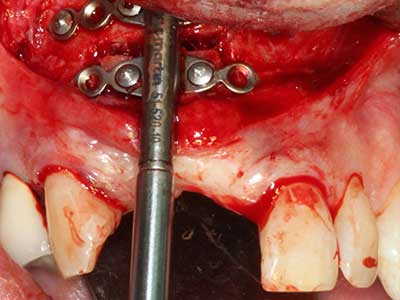

Костната тъкан е не само минерализирана структура, тя съдържа и съществено количество колагенови влакна. Това означава, че тя има не само добра компресивна сила, но и известна степен на гъвкавост, която може да се възприеме като предимство при извършване на костна аугментация. В класическата процедура по разширяване чрез костно разделяне, атрофиралият алвеоларен гребен е разделен надлъжно и внимателно разширен след достигане на подходящата остеотомна дълбочина (Фиг. 13-16), в идеалния случай без допълнително отстраняване на периостеума (Brugnami, Caiazzo et al. 2014, Stricker, Fleiner et al. 2014). Системите с винт и пластини с увеличаване на разстоянието при разширяване са доказали ефективността си при разделяне на двете костни ламели, оставайки под прага на фрактурите. В общи линии, оставащата ширина на костта от поне 3–4 mm е задължителна (Chiapasco, Zaniboni et al. 2006), за да се гарантира добра гъвкавост и достатъчно костно покритие за бъдещото поставяне на импланти. Ако е необходимо, вертикалната остеотомия на едната или двете страни може да подобри гъвкавостта. Комбинацията с допълнителни техники за аугментация, особено в букалната страна, е описана като алтернатива на класическата техника.